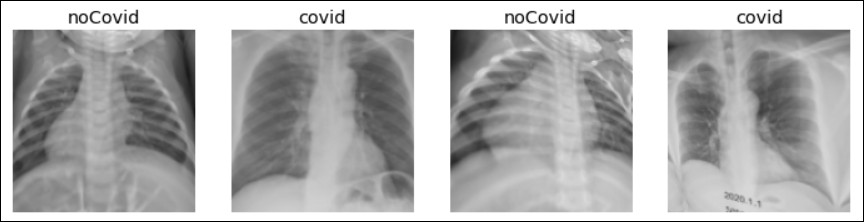

在此图像分类问题中,我将训练模型,以将X射线图像分类为COVID或No COVID类。预处理数据集已放置在单独的COVID和No COVID文件夹中(来源:ChristianTutivénGálvez)。

(‘noCovid’, tensor(1), tensor([5.4443e-05, 9.9995e-01])) – prediction